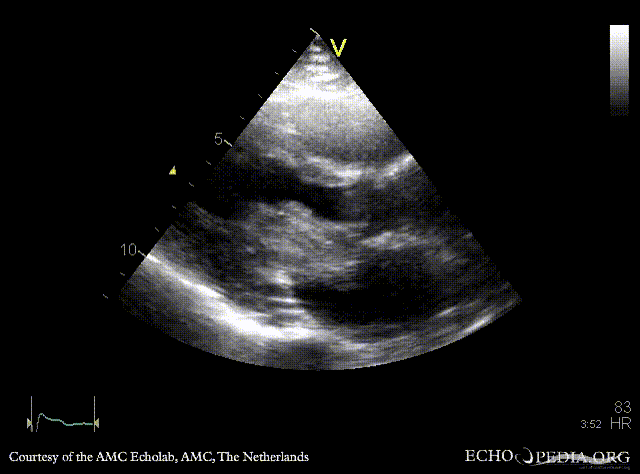

Giant myxoma in left atrium

PLAX: giant mobile myxoma in left atrium